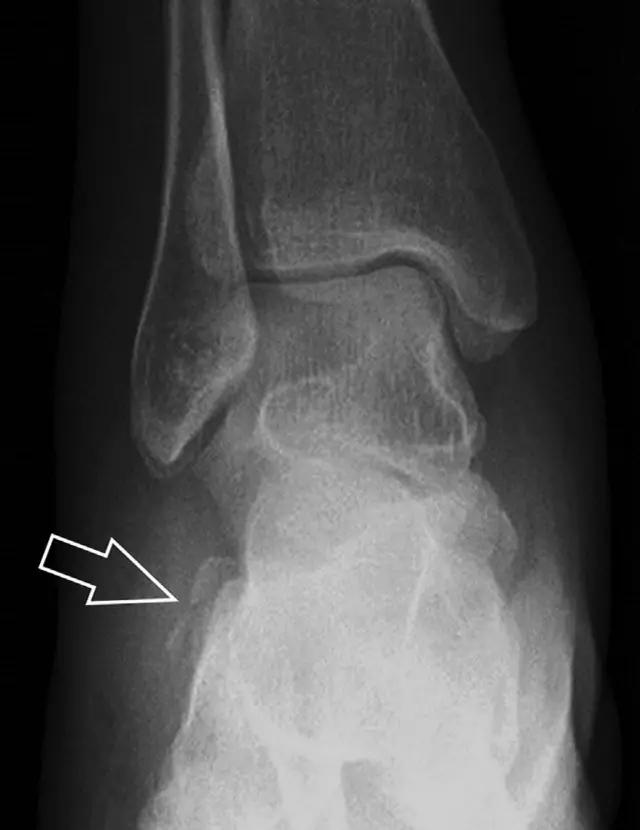

16 胫骨后踝骨折

涉及到三角韧带和外侧副韧带(LCL)的复杂性骨折常常不难发现,尤其是存在表面软组织肿胀时。然而,后胫腓韧带牵拉引起的胫骨后踝骨折则很难发现。这些骨折大小不一(图 2),却很重要,因为他们常与胫骨远端螺旋骨折有关,或者是三踝骨折的一部分。

图 2 胫骨后踝骨折。A 侧位片示来源于胫骨后踝的一个小骨折碎片(箭头),因踝部扭伤导致;B 另一位跖屈损伤的患者,侧位片示一个大骨折块(箭头)